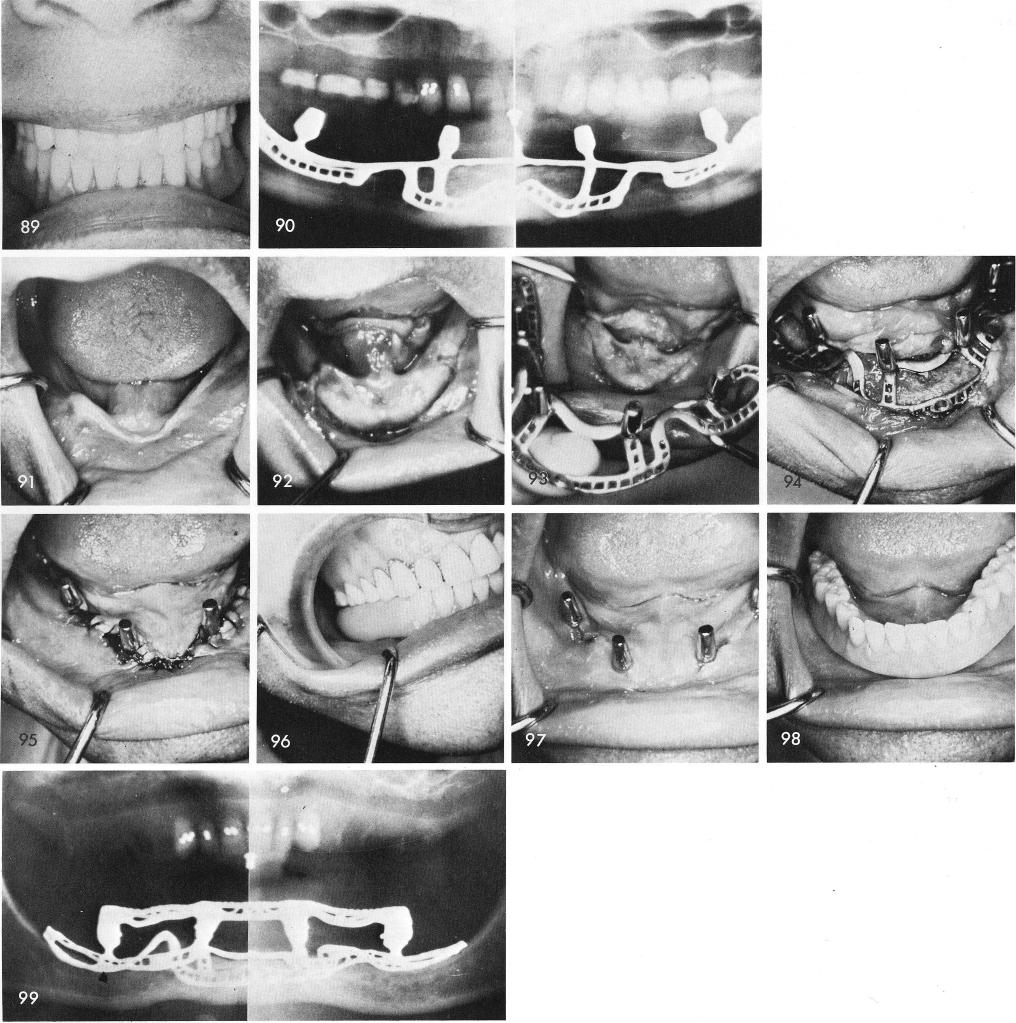

An unusual looking view of the covered mandible, fig. 91. The bone is exposed, fig. 92, and the implant fitted, figs. 93, 94, and the tissues sutured, fig. 95. The temporary acrylic stent is carefully checked for proper occlusion and must be relieved of any tissue interference, fig. 96. The tissues as they looked three weeks post-operatively, fig. 97. The completed implant denture does not touch the tissues, fig. 98. The post-operative x-ray, fig. 99.

1 Completed mandibular implant denture without touching the tissues